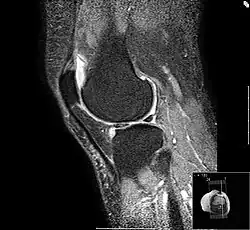

Die Darstellungstechnik ist etwas anders als auf den oberen Bildern, der Reizerguss - im Prinzip Wasser - kommt hier weiß zur Darstellung. Zu sehen ist die Verteilung der Gelenkflüssigkeit (Synovia), dazu zeigen sich, besonders am oberen Pol der Kniescheibe, Osteophyten.

Ein gesundes Knie braucht eine Valgus- oder X-Stellung von 8 Grad. Schäden am Innenmeniskus sind insbesondere bei Leistungssportlern (z. B. Fußballspielern) häufig. Wird der Meniskus verletzt, bietet sich die operative Entfernung des zerrissenen Anteils an. Das ist sinnvoll, weil das Meniskusgewebe die gleiche Oberflächenhärte hat wie der Knorpel des Gelenkes. Bleibt das Fragment im Knie, führt das in kurzer Zeit zu Knorpelschäden.